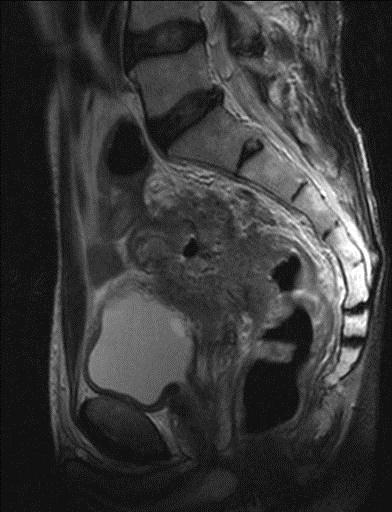

МРТ органов малого таза и наружных половых органов у мужчин – важный метод исследования, который позволяет визуализировать предстательную железу, мочевой пузырь, семенные пузырьки, прямую кишку, наружные половые органы.

Как проводится МРТ органов малого таза и наружных половых органов у мужчин?

Перед укладкой в томограф необходимо снять все металлические предметы. После этого пациент ложится на стол сканера, который постепенно перемещается в аппарат. Во время сканирования следует лежать неподвижно, чтобы получаемые изображения были четкими и неискаженными.